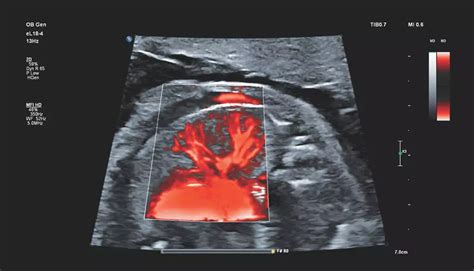

Gray-Scale, Color Doppler, Spectral Doppler, and Contrast-Enhanced ...

Philips - eL18-4

Medullary Cystic Kidney Disease Ultrasound